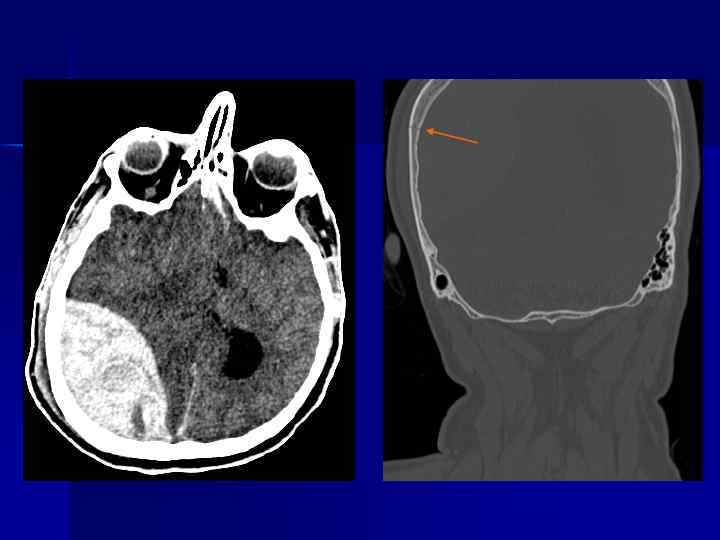

ЧМТ (5 сутки). Ушиб головного мозга с геморрагическим пропитыванием Ишемия в бассейне сонной артерии. Оскольчатый перелом свода черепа.